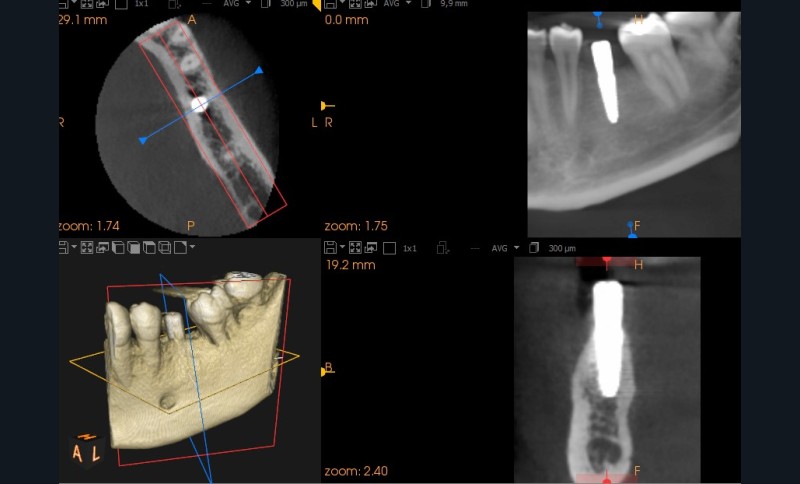

Pour cela nous décidons de poser notre implant de façon « Full guidé », c’est-à-dire planifié en amont dans une position alliant un placement optimal osseux et prothétique. Nous aurons besoin d’une empreinte numérique qui va nous fournir un fichier STL (fig. 1) , ainsi que les information sur l’os fournies par le cone-beam (CBCT) . Nous décidons à ce stade de faire modéliser le guide par une plateforme de conception (design4me) qui s’occupera du matching de nos DATA. Après validation de la planification nous recevons notre fichier (fig. 2) prêt à être imprimé localement grâce à une imprimante 3D (Nextdent).

La particularité du « Full guidé » est que tout les forets seront guidés et l’implant lui-même sera placé au travers du guide chirurgical. (fig 3 , radio post-opératoire).